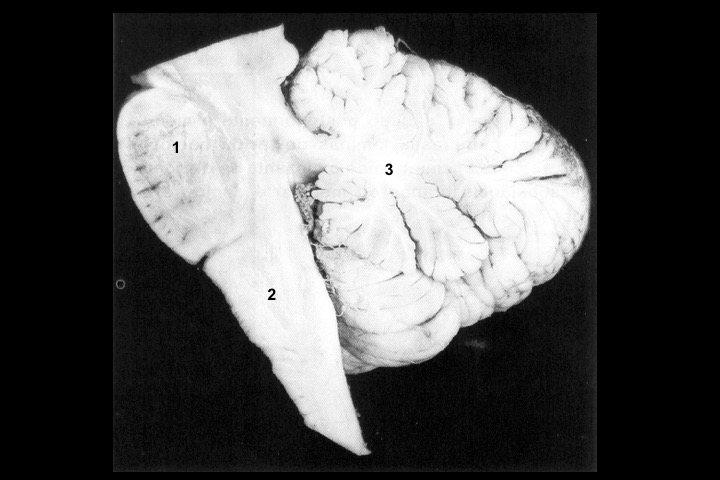

O Prof. Emérito da UFRJ Dr. Adalmir Morterá Dantas está disponibilizando através de nosso website e de nosso canal youtube (cursobom) o Museu de Neuroanatomia, no intuito de promover esta área de conhecimento junto aos estudantes de Medicina.

As figuras são apresentadas em 4 vídeos no youtube e podem ser obtidas via download clicando-se na figura em questão.